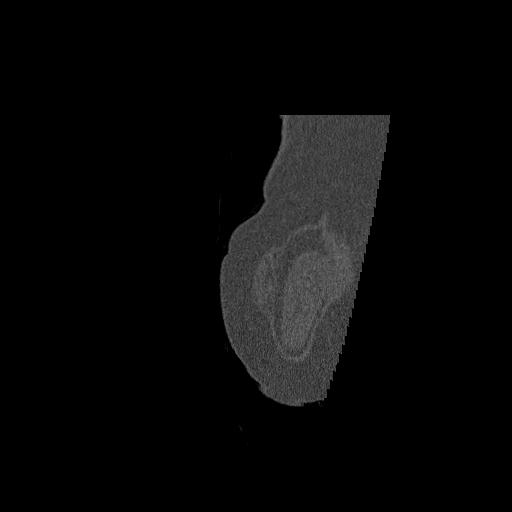

102755 1/4 2R 1/15 2R 右足関節 68歳女性 右三果脱臼骨折